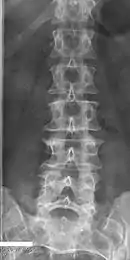

Anatomical terms of bone

The lumbar vertebrae are, in human anatomy, the five vertebrae between the rib cage and the pelvis. They are the largest segments of the vertebral column and are characterized by the absence of the foramen transversarium within the transverse process (since it is only found in the cervical region) and by the absence of facets on the sides of the body (as found only in the thoracic region). They are designated L1 to L5, starting at the top. The lumbar vertebrae help support the weight of the body, and permit movement.